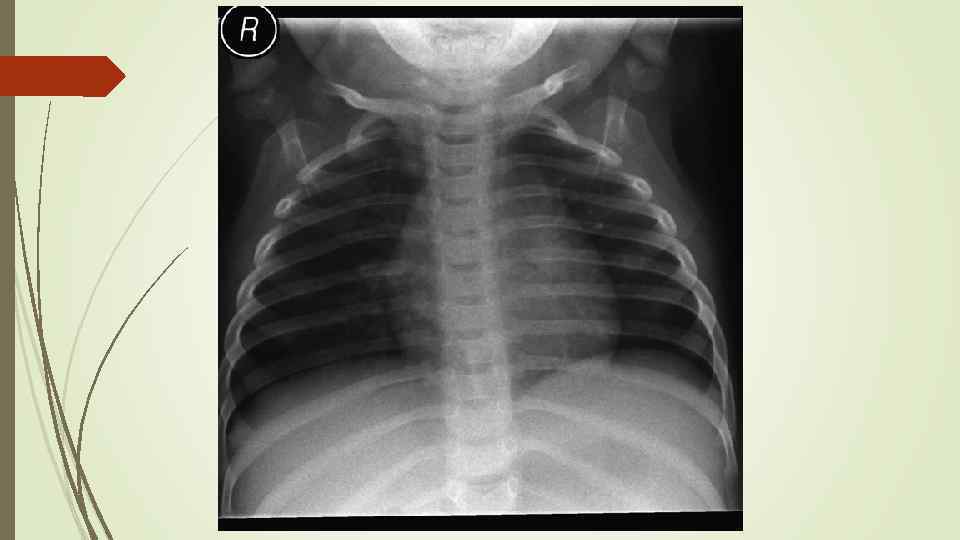

Бронхопневмония Характерно наличие двухсторонних множественных очаговых теней. Контуры очагов нечеткие, интенсивность тени небольшая. Инфильтрация неоднородна. Мелкие, малоинтенсивные очаги не всегда выявляются на снимках. Легочный рисунок усилен на всем протяжении легких. Корни расширены, не структурны. Как правило, отмечается реакция плевры, могут быть и экссудативные плевриты.

Бронхопневмония Характерно наличие двухсторонних множественных очаговых теней. Контуры очагов нечеткие, интенсивность тени небольшая. Инфильтрация неоднородна. Мелкие, малоинтенсивные очаги не всегда выявляются на снимках. Легочный рисунок усилен на всем протяжении легких. Корни расширены, не структурны. Как правило, отмечается реакция плевры, могут быть и экссудативные плевриты.

bronhopneumoni

bronhopneumoni